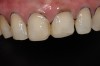

Fig 14. Postoperative view showing additively restored palatal surfaces of upper anteriors.

Figure 14

A few weeks later, the facial veneers were bonded directly to the underlying enamel. A postoperative photograph (Figure 11) revealed the restored harmony of the patient’s smile and the occlusal contacts in MIP (Figure 12). The palatal surfaces restored with nanofilled composite resin developed good anterior guidance that was harmonized to the patient’s chewing cycle (Figure 13 and Figure 14).19